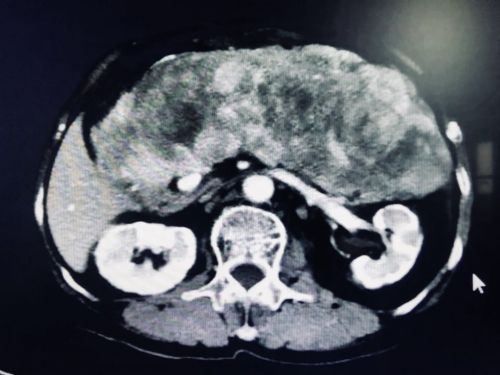

巨大的肿瘤将正常肝脏挤压变形。

入院后,首席专家吴金术教授带领胰脾外科团队对李群英的病情进行多次会诊,反复讨论后制定了周密的手术方案。“肿瘤巨大,累及多个脏器,供血血管也很丰富”,吴金术教授介绍,李群英体内的肿瘤几乎占据她整个腹腔,不仅如此,腹主动脉、腹腔动脉干、肝固有动脉、脾动脉、肠系膜上动脉、肠系膜上静脉、腔静脉、门静脉等重要的大血管与肿瘤致密粘连,手术必须在保证肿瘤完整的情况下,小心翼翼地分离肿瘤和上述血管,然后将肿瘤和受累脏器完整切除,难度空前。

9月20日,陈梅福、成伟、朱朝庚、刘昌军、李国光等医护人员在吴金术教授的指导下轮番上阵,历时10小时,为李群英成功切除一个约30×40×10cm3大小、重达3.3公斤的腹膜后脂肪肉瘤,被肿瘤累及的胰腺、脾脏、95%的胃、胆囊、胆总管下段、十二指肠、空肠上段、横结肠等8个脏器也被一同切除,仅切下的肠子就有六七十厘米长,并为她重建消化道。